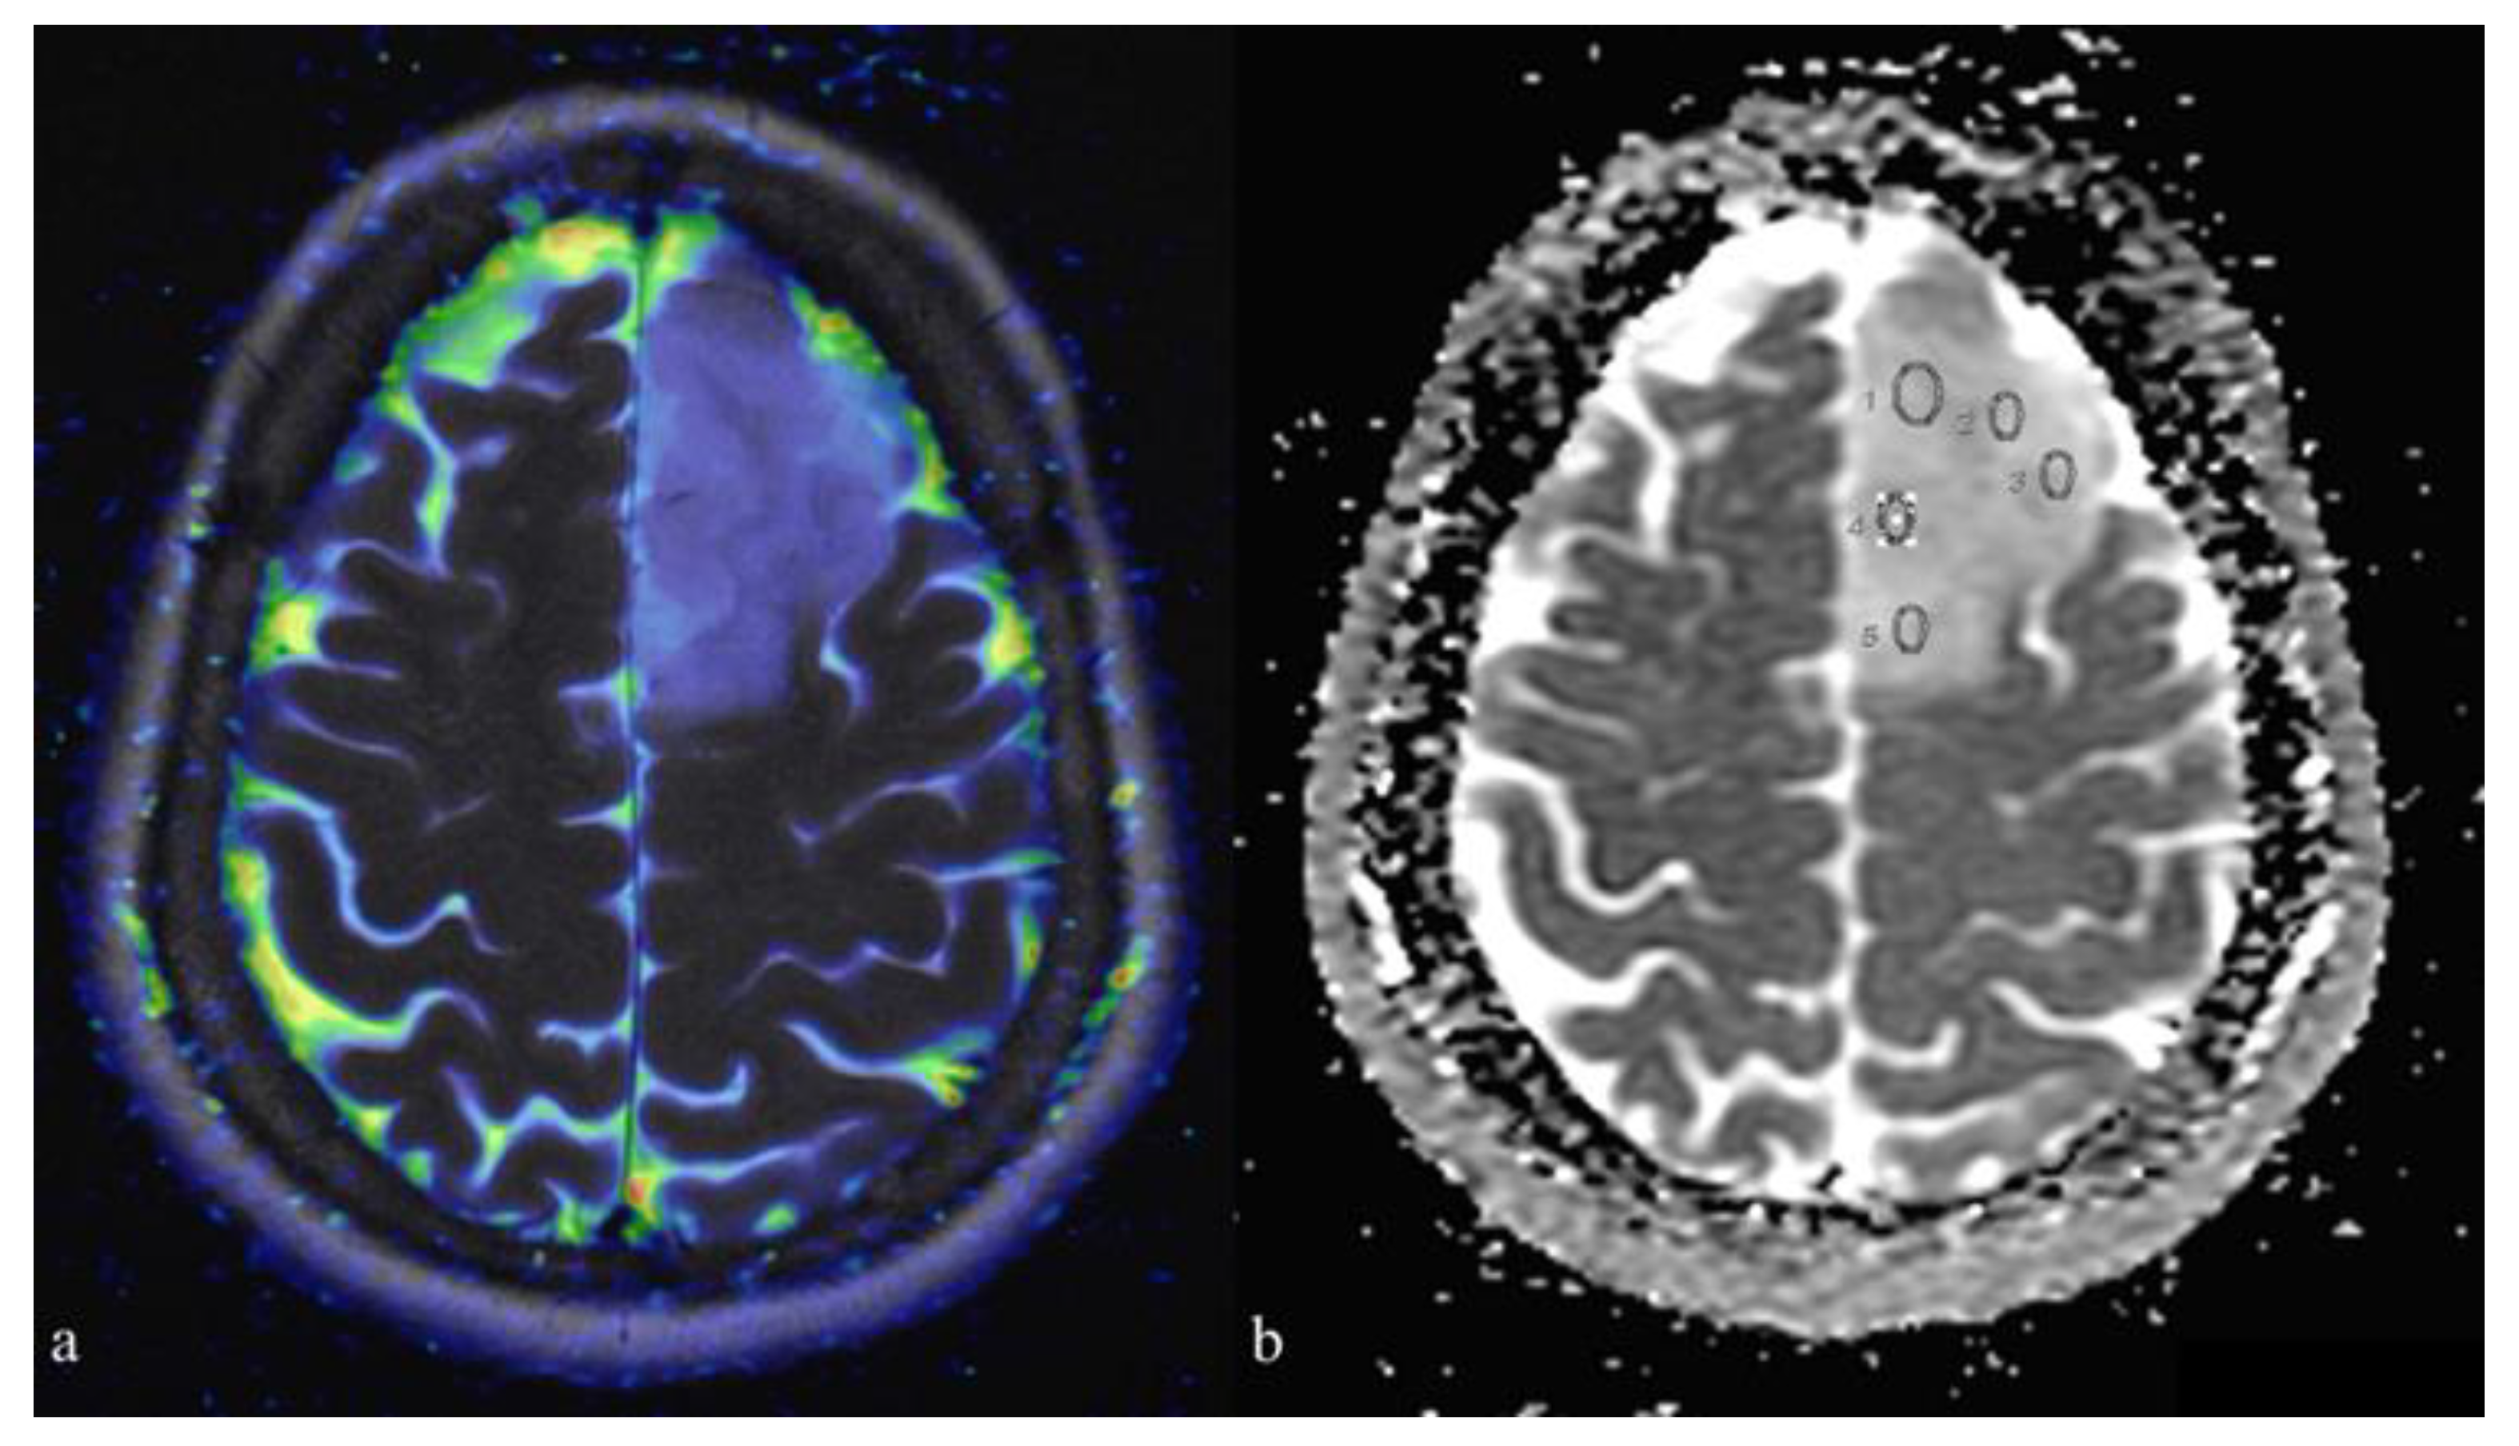

| ADCm | 1.21 ± 0.19 | 0.90 ± 0.08 | 0.0004 (* 0.0012) |

| rADCm | 1.77 ± 0.33 | 1.33 ± 0.13 | 0.0021 |